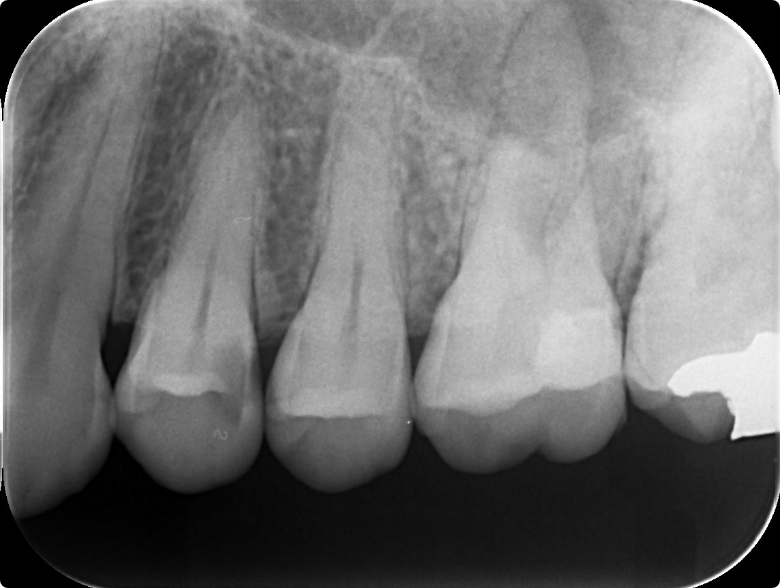

奥歯の根管治療を行った症例

BEFORE

症例概要

年代、性別

49歳女性

主訴

左上の歯茎から膿がでている

診断

根尖性歯周炎

治療内容

感染根管治療、ファイバーポストを用いた支台築造、フルジルコニアクラウン装着

治療期間

2ヶ月程度

治療リスク

噛み合わせの状態によっては歯根破折を起こすことがある

治療費用

242,000円(税込)